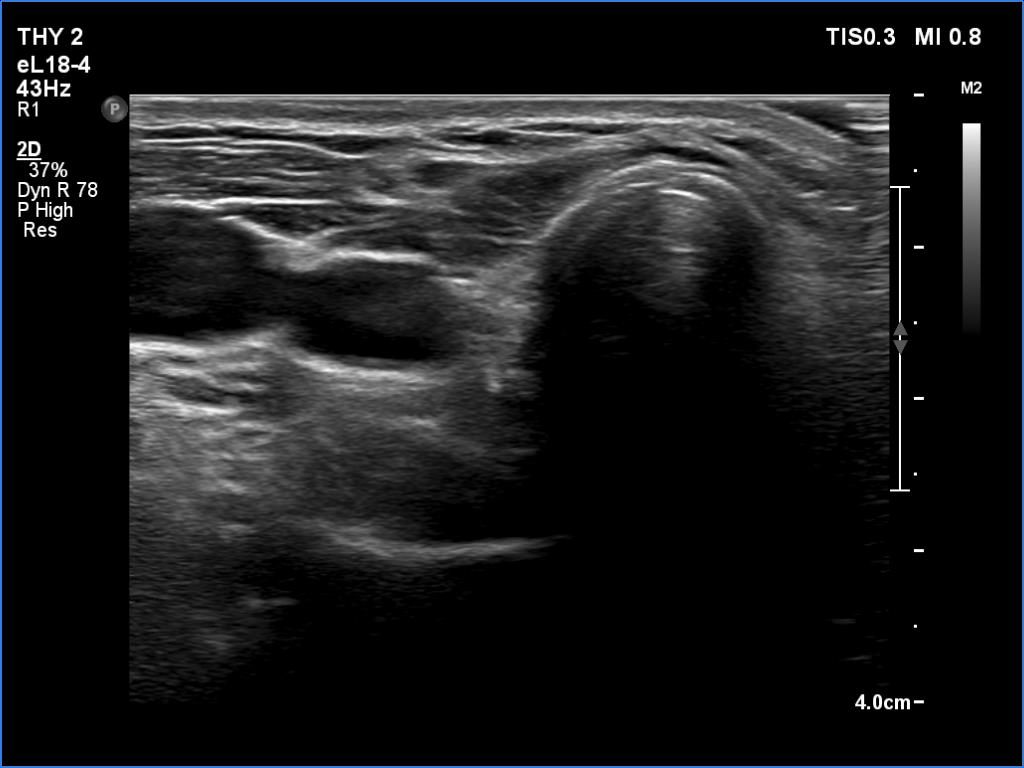

Ultrasonography. The right lobe was replaced by connective tissue. The left lobe was composed of a central hypoechoic mass which was surrounded with thin echonormal tissue. The hypoechoic part of the lobe was composed of smaller discrete lesions. The vascularity was significantly increased both on color Doppler mode and on microflow imaging.

1. A central hypoechoic mass surrounded with an echonormal tissue is one of the most common presentations of a subtotally resected thyroid.